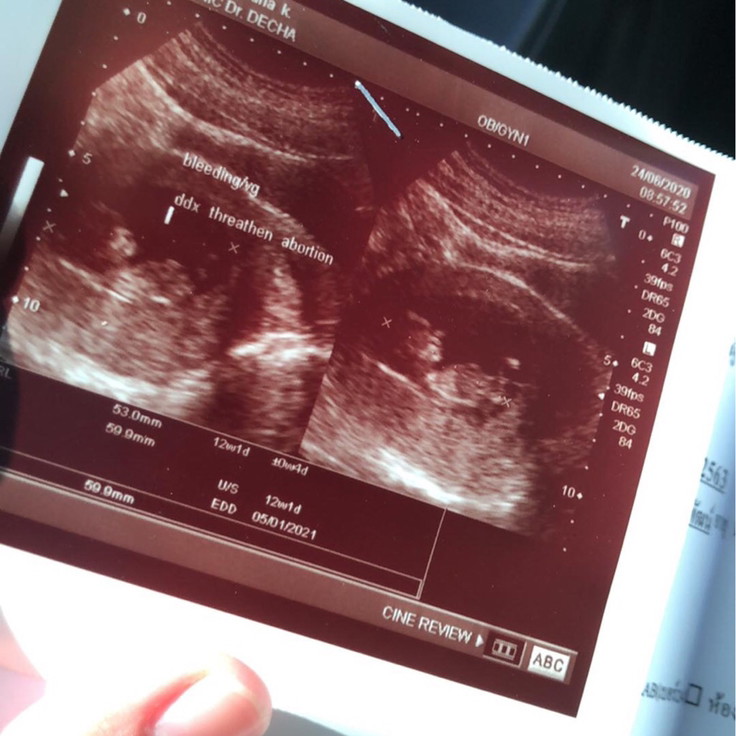

13 w เองจ้าา ❤️

บ้านนี้ 13 วีคค่ะ